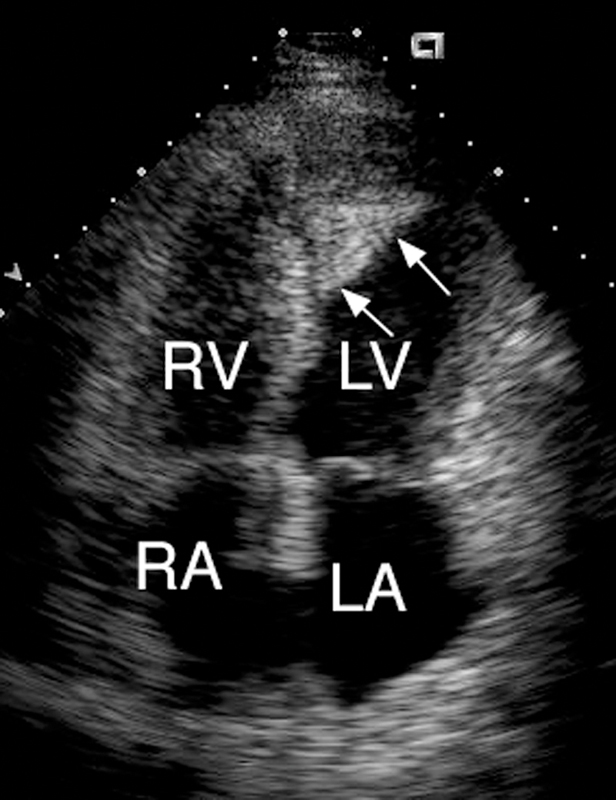

فحوصات تشخيصية لبعض امراض القلب والشرايين التاجية